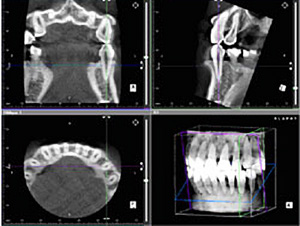

歯科用CTを導入

従来の歯科用レントゲンでは、平面画像からの情報しか得ることができませんでした。

歯科用CTを使うことで、従来のレントゲンでは得ることができなかった歯の周囲の形状や歯根の先の状態、歯と神経の位置関係などの情報を正確に知ることができるようになりました。